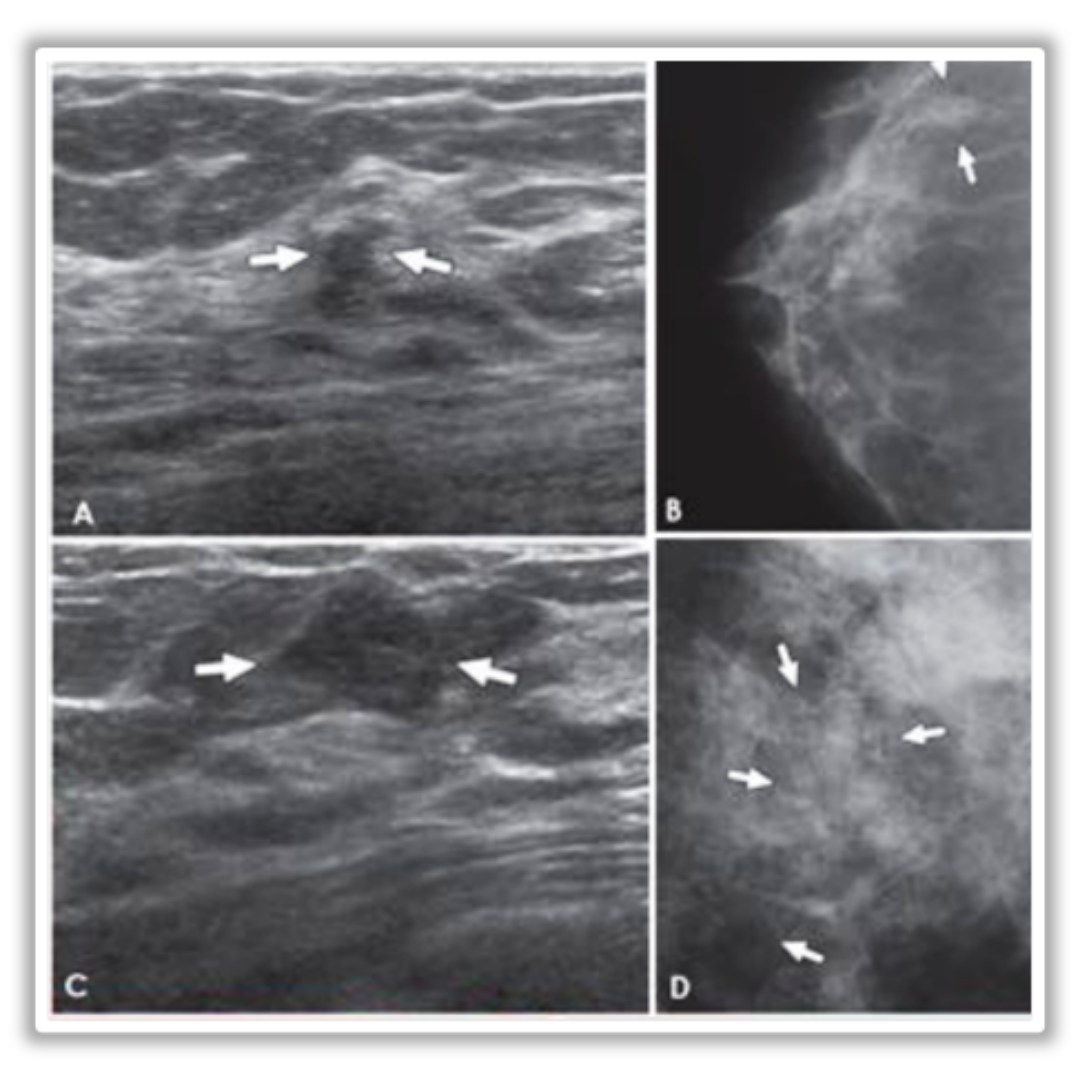

Imagen 11: A y B Lesión hipoecogénica de margen irregular y orientación antiparalela, que en la mamografía se corresponde con una densidad focal asimétrica en CSE, con diagnóstico de hiperplasia ductal atípica. C y D masa ovalada, hipoecogénica de margen angulado, que en mamografía se asociaba a microcalcificaciones pleomórficas, con diagnóstico de hiperplasia ductal atípica.